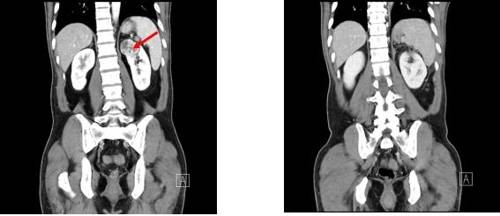

신장질환 진단에 있어 복부초음파는 가장 흔하고 비침습적이며 많은 정보를 얻을 수 있고 복막 내 다양한 장기를 관찰할 수 있다. 최근에는 건강검진 시 복부 초음파 검사를 자주 시행하여 새로운 종양을 조기에 발견하는 경우가 많습니다. 복부초음파에서 신장에 낭종이 발견되면 단순낭종인지 복합낭종인지 고형종양인지 구분할 수 있다고 합니다. 조영제를 사용한 CT 스캔이 권장됩니다.신장 낭종 치료

대부분의 단순 신장 낭종(신장 낭종)은 특별한 치료가 필요하지 않으며 정기적인 추적 검사로 충분합니다. 그러나 신장 낭종(콩팥낭종)이 매우 크고 관련 증상이 있는 경우에는 대증적 치료가 필요합니다. 단순 신장 낭종(신장 낭종)은 신장이 있는 쪽에 구멍을 뚫어 카테터를 삽입하고 내부의 용액을 배출한 후 카테터를 통해 약물을 주입하여 낭종이 융합되도록 함으로써 치료합니다.

드물게 낭성 신장암이 의심되는 경우 신장을 제거하는 수술이 필요할 수 있습니다. 이때 수술은 신낭종(콩팥낭종)의 크기에만 의존하지 않는다고 합니다. 신장 낭종(신장 낭종 또는 신장 낭종)으로 인한 합병증이 있거나 영상 검사에서 악성 가능성이 있는 경우 수술을 고려할 수 있습니다.